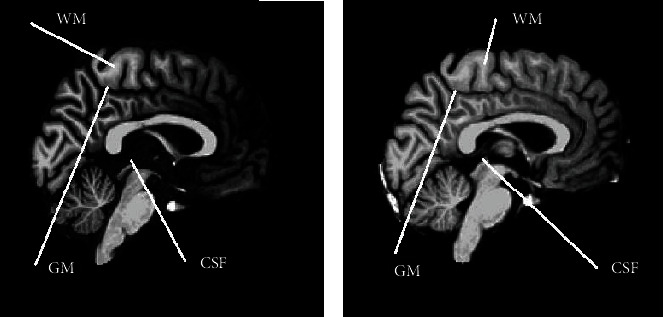

Background: The 3D T1W turbo field echo sequence is a standard imaging method for acquiring high-contrast images of the brain. However, the contrast-to-noise ratio (CNR) can be affected by the turbo factor, which could affect the delineation and segmentation of various structures in the brain and may consequently lead to misdiagnosis. This study is aimed at evaluating the effect of the turbo factor on image quality and volumetric measurement reproducibility in brain magnetic resonance imaging (MRI).

Methods: Brain images of five healthy volunteers with no history of neurological diseases were acquired on a 1.5 T MRI scanner with varying turbo factors of 50, 100, 150, 200, and 225. The images were processed and analyzed with FreeSurfer. The influence of the TFE factor on image quality and reproducibility of brain volume measurements was investigated. Image quality metrics assessed included the signal-to-noise ratio (SNR) of white matter (WM), CNR between gray matter/white matter (GM/WM) and gray matter/cerebrospinal fluid (GM/CSF), and Euler number (EN). Moreover, structural brain volume measurements of WM, GM, and CSF were conducted.

Results: Turbo factor 200 produced the best SNR (median = 17.01) and GM/WM CNR (median = 2.29), but turbo factor 100 offered the most reproducible SNR (IQR = 2.72) and GM/WM CNR (IQR = 0.14). Turbo factor 50 had the worst and the least reproducible SNR, whereas turbo factor 225 had the worst and the least reproducible GM/WM CNR. Turbo factor 200 again had the best GM/CSF CNR but offered the least reproducible GM/CSF CNR. Turbo factor 225 had the best performance on EN (-21), while turbo factor 200 was next to the most reproducible turbo factor on EN (11). The results showed that turbo factor 200 had the least data acquisition time, in addition to superior performance on SNR, GM/WM CNR, GM/CSF CNR, and good reproducibility characteristics on EN. Both image quality metrics and volumetric measurements did not vary significantly (p > 0.05) with the range of turbo factors used in the study by one-way ANOVA analysis.

Conclusion: Since no significant differences were observed in the performance of the turbo factors in terms of image quality and volume of brain structure, turbo factor 200 with a 74% acquisition time reduction was found to be optimal for brain MR imaging at 1.5 T.